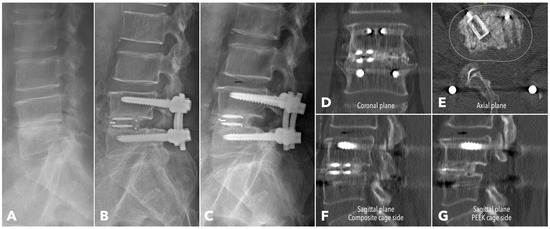

Improved Clinical and Radiological Outcomes with Double-Cage Biportal Endoscopic Transforaminal Lumbar Interbody Fusion: A Comparative CT-Based Study

by Yu-Hao Huang and Jwo-Luen Pao

Diagnostics 2025, 15(20), 2652; https://doi.org/10.3390/diagnostics15202652 - 21 Oct 2025

Cited by 1 | Viewed by 1504

Abstract

Background/Objectives: When transitioning from an older surgical technique to a newer one, we expect improved treatment outcomes and fewer complications. However, direct comparative studies to confirm these advantages are often lacking. Tubular minimally invasive transforaminal lumbar interbody fusion (MISTLIF) has been widely [...] Read more.

Background/Objectives: When transitioning from an older surgical technique to a newer one, we expect improved treatment outcomes and fewer complications. However, direct comparative studies to confirm these advantages are often lacking. Tubular minimally invasive transforaminal lumbar interbody fusion (MISTLIF) has been widely used, but limitations in visualization and endplate preparation may compromise fusion quality. Biportal endoscopic TLIF (BETLIF), a more recent alternative, offers enhanced magnification and superior hemostasis. Still, CT-based comparative data on fusion integrity remain limited. To evaluate the clinical and radiological outcomes following a chronological transition from MISTLIF to BETLIF, using thin-slice CT to assess fusion integrity. Methods: This retrospective study analyzed 179 patients treated by a single surgeon between January 2018 and May 2021. The first 90 cases underwent MISTLIF, followed by 89 BETLIF procedures. Clinical outcomes included Visual Analog Scale (VAS), Oswestry Disability Index (ODI), and Japanese Orthopedic Association (JOA) scores. Radiological assessments at one year postoperatively (X-ray and thin-slice CT) included disc height, segmental lordosis, Bridwell fusion grade, cage subsidence, and subchondral osteolysis. Results: BETLIF was associated with significantly shorter hospital stays (5.7 vs. 7.4 days) and fewer transfusions (0% vs. 14.7%). BETLIF showed significantly better ODI (12.7 vs. 23.5), JOA scores (26.4 vs. 20.6), and comparable VAS improvement. Radiologically, BETLIF had significantly higher fusion rates (93.3% vs. 82.4%), greater disc height restoration, and lower rates of cage subsidence (5.0% vs. 13.7%) and osteolysis (13.3% vs. 52.9%). Conclusions: BETLIF demonstrated superior clinical and radiological outcomes, likely due to enhanced endoscopic visualization and precise endplate preparation. Full article

(This article belongs to the Special Issue Diagnosis and Management of Spinal Diseases)

Show Figures

Figure 1